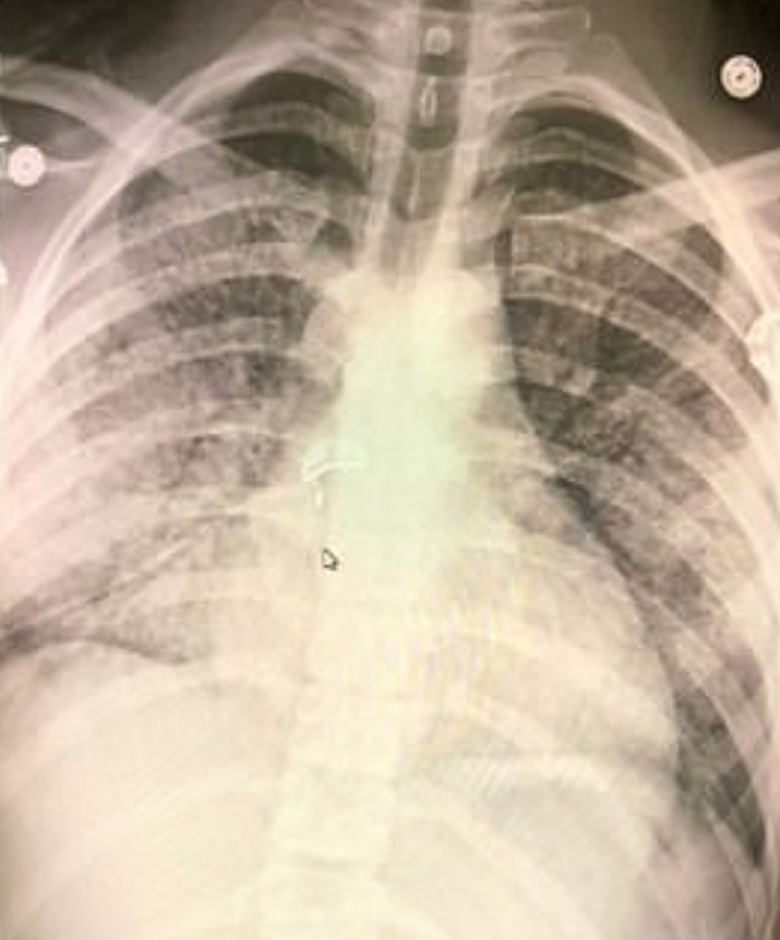

Các bác sĩ đã tiến hành chụp CT dạ dày, chụp X-quang phổi thì mới phát hiện ra được nguyên nhân thực sự. Trong phim X-quang cho thấy, phổi của Adam bị tổn thương nghiêm trọng "trông giống như phổi của một người 70 tuổi".

"Đó là bệnh phổi ở giai đoạn nghiêm trọng, tuy nhiên điều này lại xảy ra với một người trẻ tuổi. Bệnh nhân cảm thấy khó thở và thở rất nhiều", bác sĩ Stephen Amesbury nói.